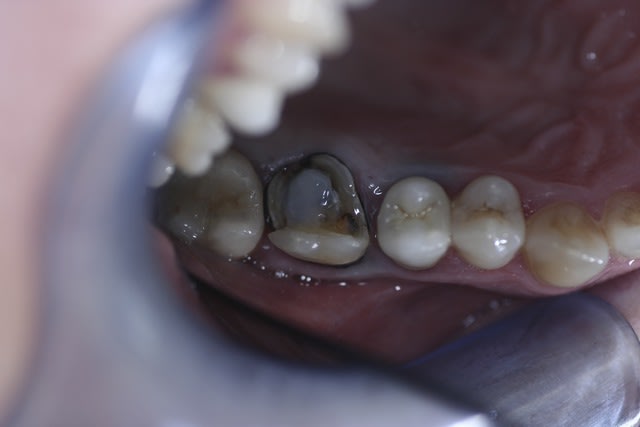

Bonjr! récente recrue sur le forum,jsuis ortho exclu et mon chir dent a proposé à mon homme un IC et une ccm pour sa 45... ça me semble un peu invasif...

-endo RAS bien que vieille

-pan lingual intact et le vestib. quasi

(quand c'est les siens bizarrement on bugue...)

Bon d'ac. dent dévitalisée=fragile=risque de fracture blabla

Perso elle pas belle (noircie) mais c'est la sienne et il est assez couronné comme ça

qu'est ce que vs en pensez? des Idées?

Il aurait fallu une photo en vue occlusale. D'après ce que je vois, un joli composite direct doit être largement suffisant. Les prémolaires du bas sont des dents qui se cassent rarement, surtout s'il n'y a qu'une cavité proximale et non MOD (en plus, largement supragingivale)

Il n'y a pas qq chose de louche au mésial de la 47 ?

et comme ceramik, il y a un truc louche sur 47

Refaire aussi la 47 (reprise de carie) et la 46 qui sont dégueulasses.

Pour la 45, un truc sans tenon (soir un compo direct avant de prendre l'empreinte pour 46, soit un inlay).